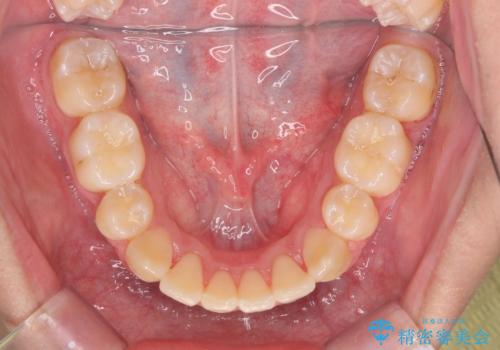

上下の前歯の重なりが大きく(過蓋咬合)時間がかかりましたが、しっかり浅く仕上げることができました。

矯正をしてよかったと大変喜んでおられました。